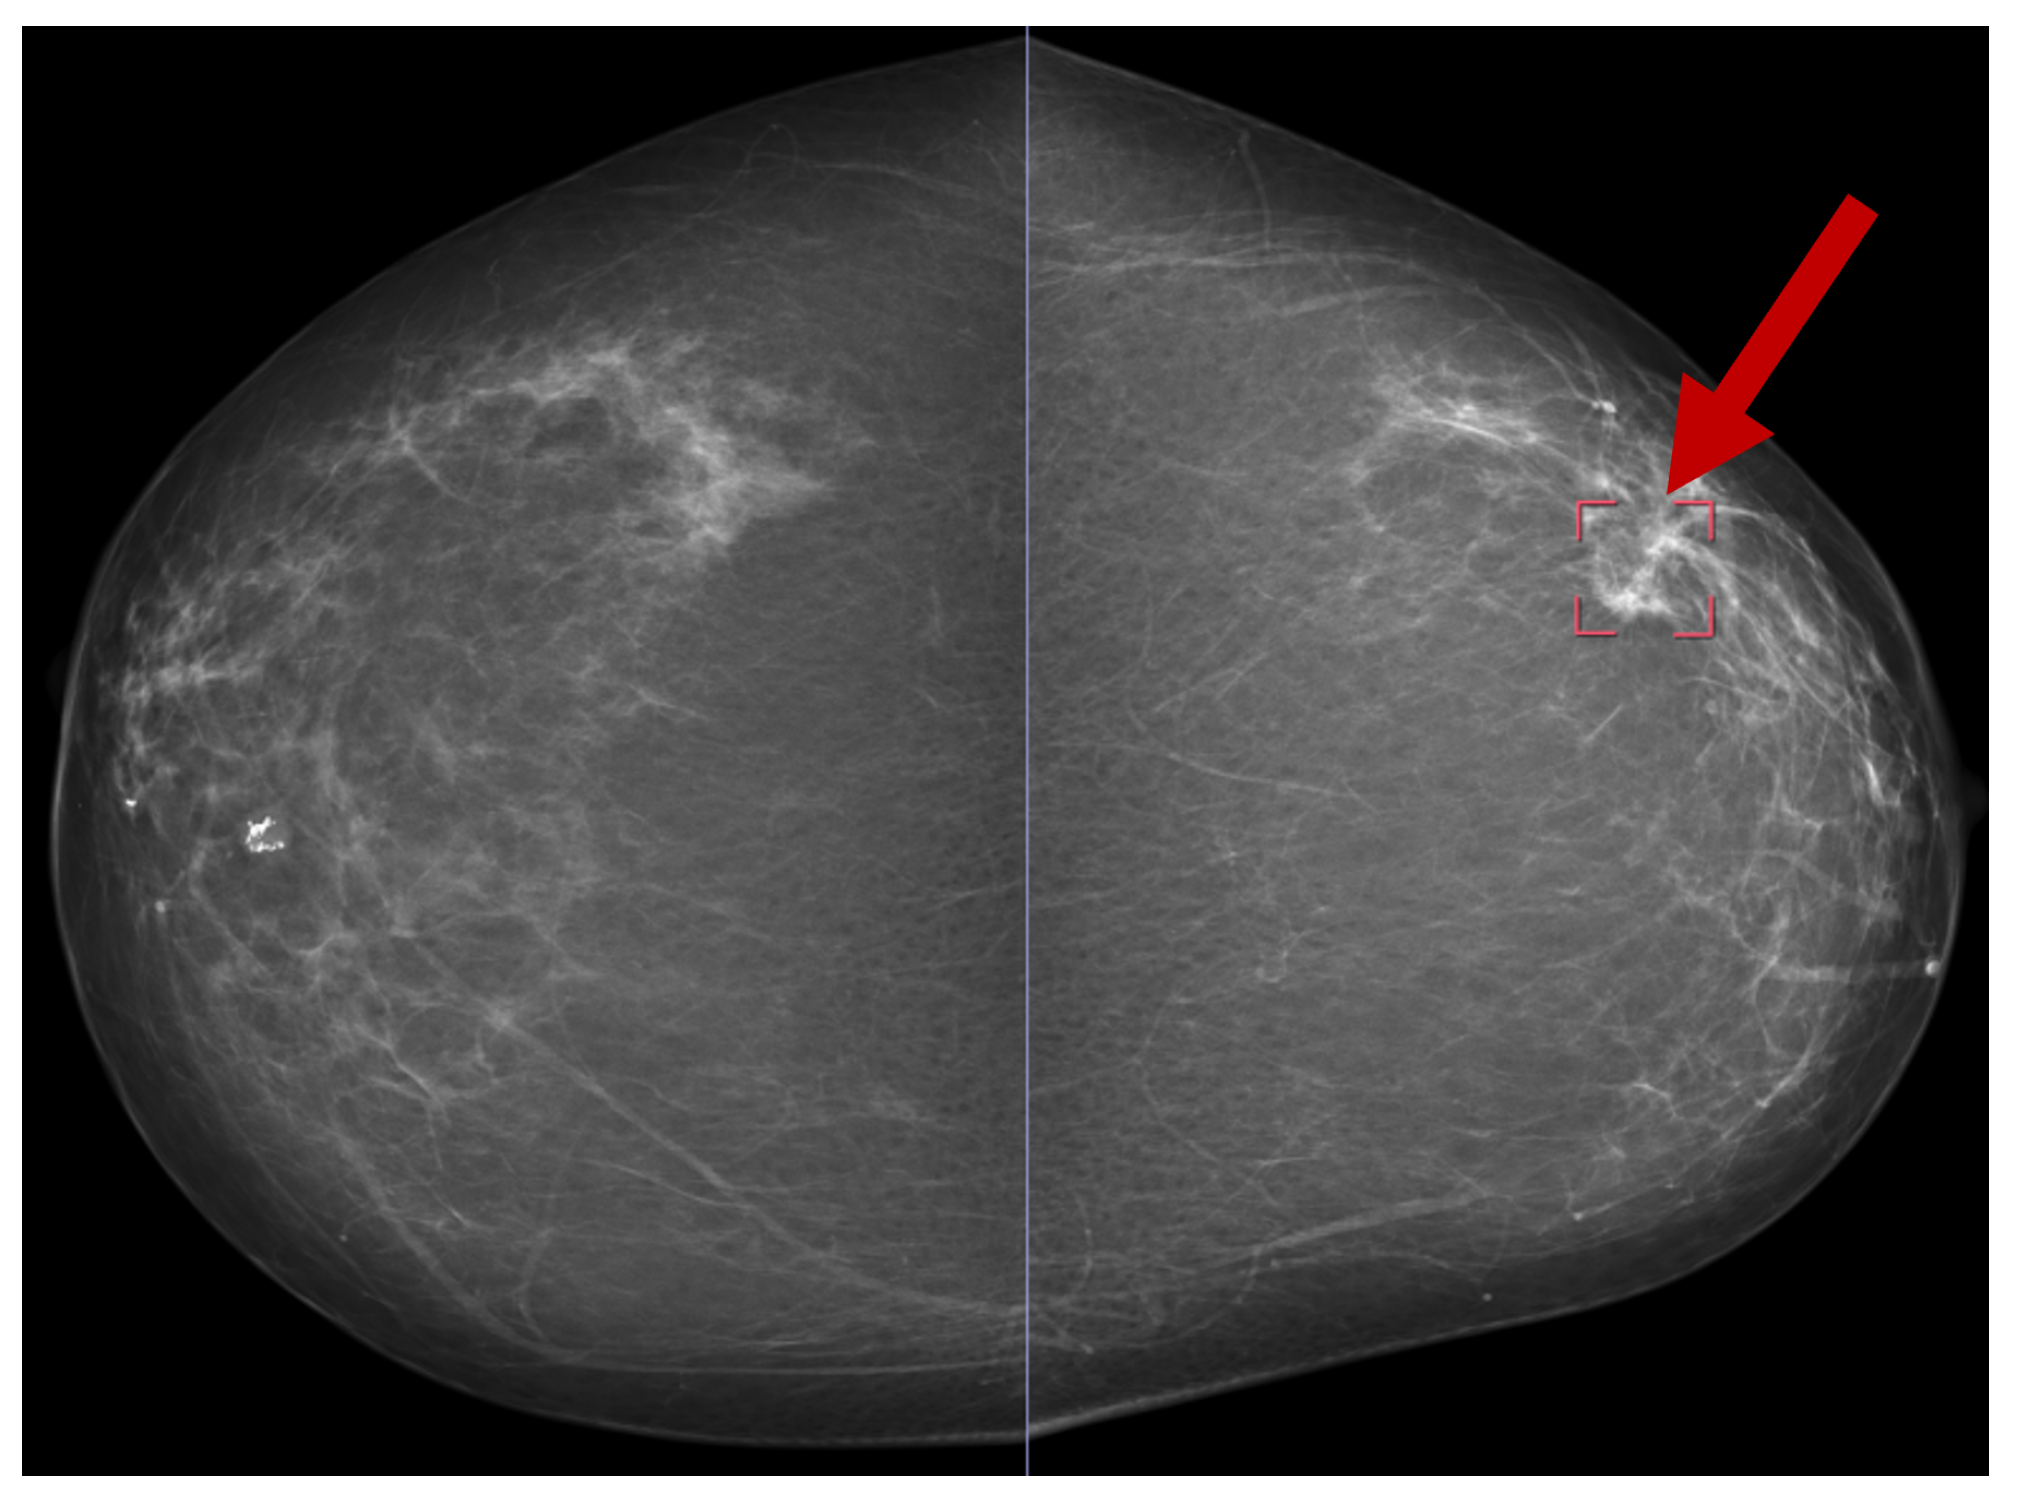

8.1. Mammogram Image-Based Breast Cancer Detection

Several publicly available datasets are widely used for mammogram image-based BC detection, including the Curated Breast Imaging Subset of DDSM (CBIS-DDSM) [69], the Digital Database for Screening Mammography (DDSM) [70], the Mammographic Image Analysis Society (MIAS) dataset [71], and the INbreast dataset [30]. Figure 13 shows a sample mammogram image with a marked areaindicated by the red square box on the right side highlighting a potential abnormality for further analysis.

Figure 13.

A sample mammogram image [72].